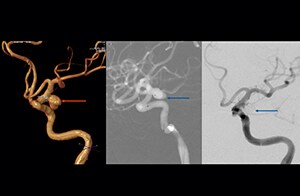

“The 3D TOF MR angiograms are obtained by using 3D T1- weighted FFE sequences (TR 35 ms, TE 7 ms, flip angle 20 degrees, field of view 250 × 190 × 108 mm, matrix 732 × 1024, four slabs, 180 slices of 0.8 mm thickness, acquisition time 8:56 minutes). On our Achieva 3.0T MRI system with an 8-channel head coil, 3D TOF is easy to use and the background signal suppression is very good. Maximum intensity projections (MIPs) and volume-rendered images are reconstructed from the data. We use a single-artery highlighting method to reduce arterial overlay. The method can also be used for carotids or other small intracranial vessels.”

“Advances in MR imaging, the high SNR and spatial resolution of 3.0T, increasing observer experience and improved postprocessing techniques have improved the capabilities of MRA over the last decade. We found that 3D TOF MRA provides excellent images for the visualization of small cerebral aneurysms which enables us to accurately diagnose, and this accuracy appears to be similar to that obtained with DSA according to data from a 2014 study," [2] Dr. Li says. “Aneurysm location can influence how easy it is recognized. Infundibula can mimic aneurysms, adding to the difficulty of interpretation. On MIP images, small aneurysms can also be easily misinterpreted when the aneurysm overlaps with the vessel. This is why in our method we are viewing the images from multiple angles.” “In the hundreds of patients with aneurysms that we scanned, we saw no significant differences in accuracy, sensitivity or specificity among the locations. [2] We think this is the result of technical advances in image acquisition and postprocessing algorithms.”